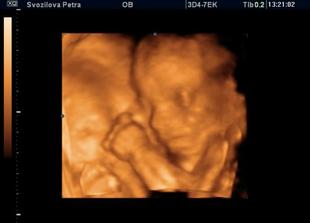

Nase miminko